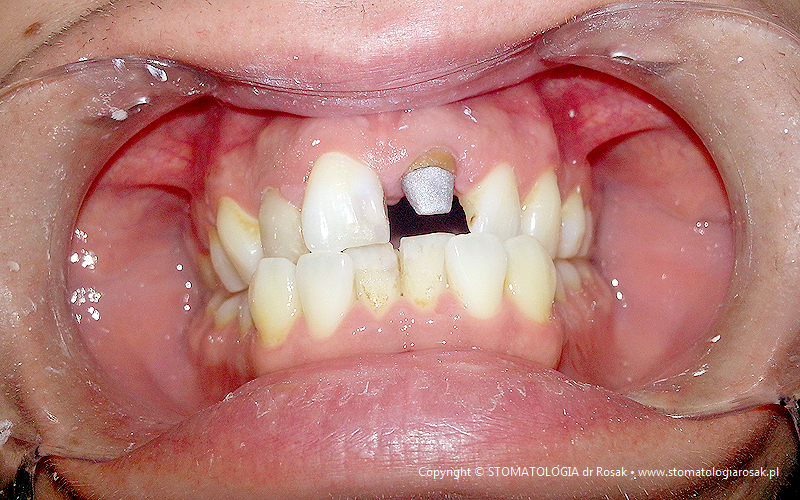

12. Pacjent zgłosił się celem usunięcia zniszczonego korzenia zęba jedynki. Zdecydowano się uratować korzeń !!!

| 12a. Pacjent przed leczeniem |

12b. Zacementowano rusztowanie stanowiące podporę dla przyszłej korony tzw. wkład koronowo-korzeniowy |

| 12c. Gotowy wkład koronowo-korzeniowy lany |

12d. Gotowa korona porcelanowa na metalu |